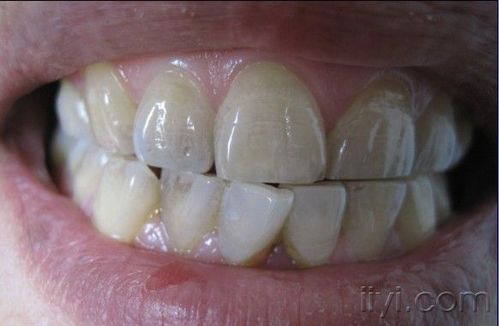

2. 为什么牙齿根尖术后会发黑?

牙齿根尖术后发黑是因为手术过程中使用的药物会对牙齿造成影响。这些药物中的氧化铁颗粒在手术后会残留在牙齿内部,随着时间的推移,会逐渐转化为黑色物质,从而导致牙齿变黑。